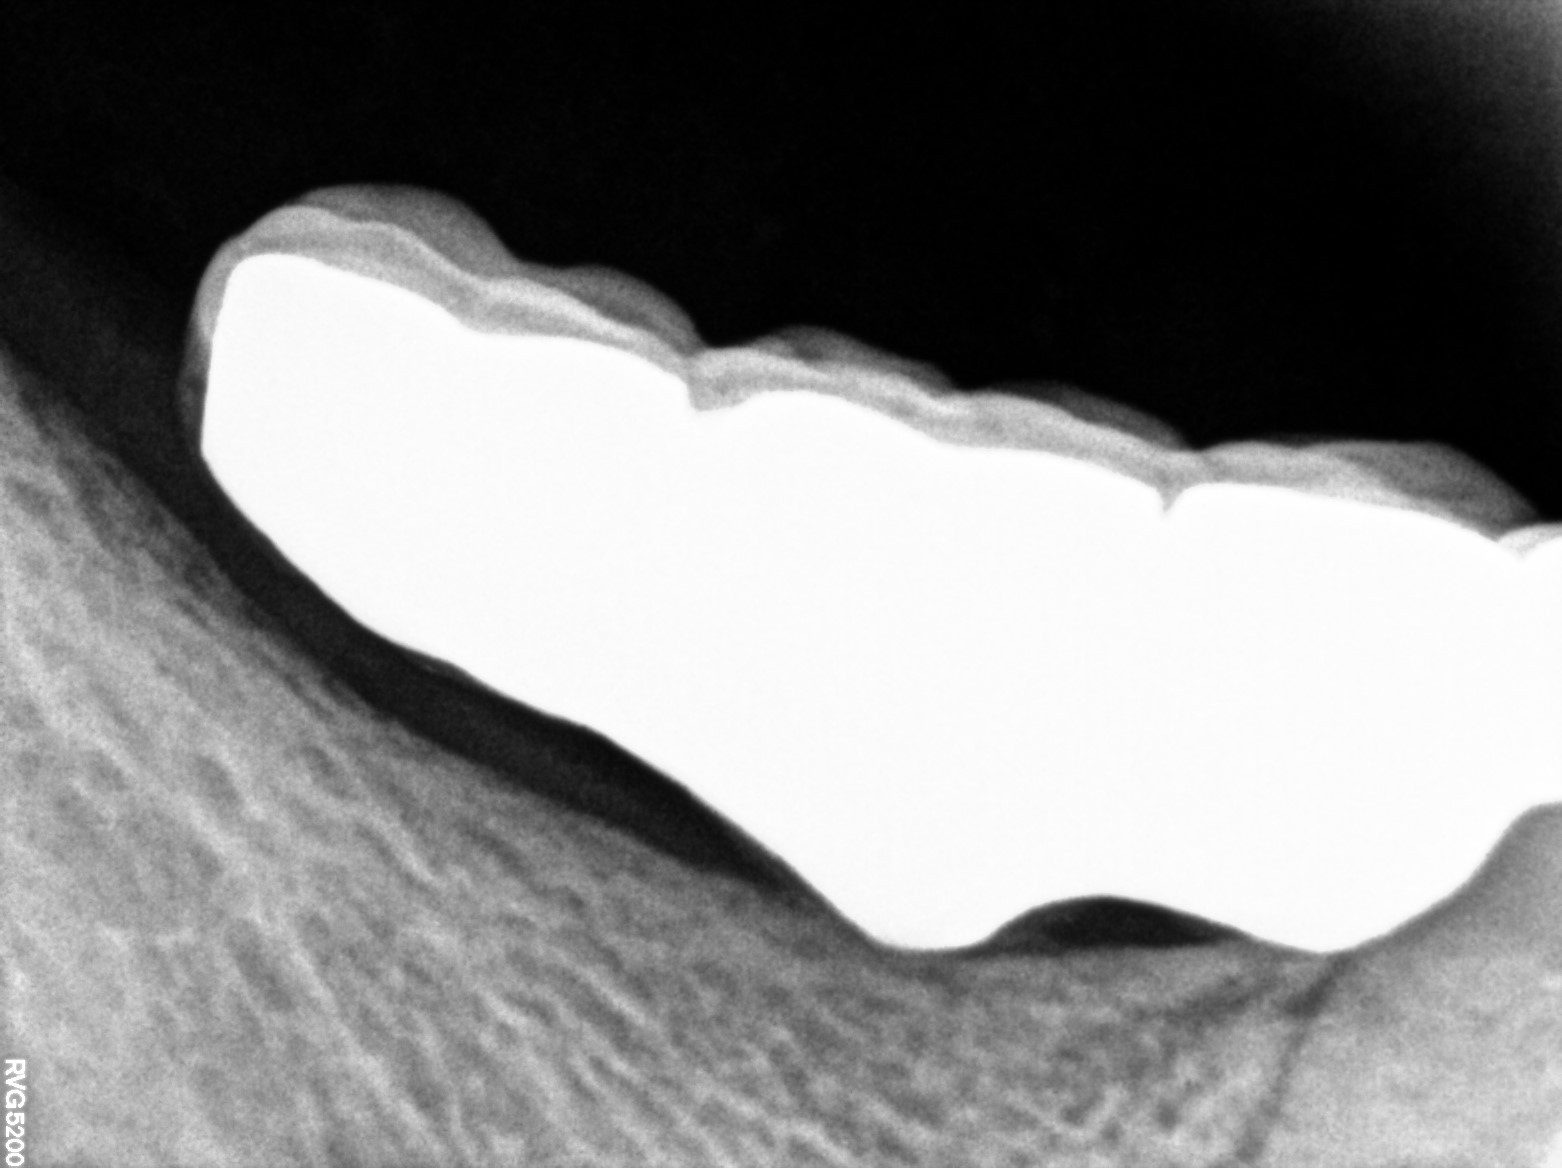

Dental Radiographs FHIR: DocumentReference · LOINC 24641-7

xray_1763362538_4.jpg

24641-7